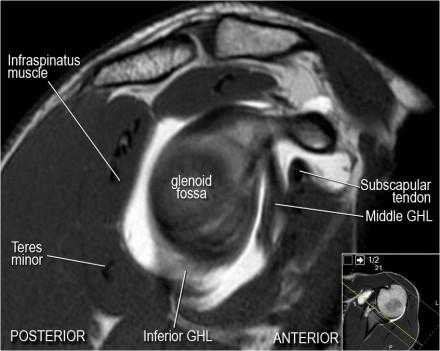

Изображение передних отделов плечевого сустава.

Нормальная анатомия плечевого сустава в аксиальных изображениях и контрольный список.

- поищите os acromiale, акромиальную кость (добавочная кость, расположенная у акромиона)

- обратите внимание что ход сухожилия надостной мышцы параллелен оси мышцы (это не всегда так)

- обратите внимание что ход сухожилия длинной головки двуглавой мышцы в области прикрепления направлен на 12 часов. Область прикрепления может быть различной ширины.

- обратите внимание на верхние отделы суставной губы и прикрепление верхней плече-лопаточной связки. На данном уровне ищется SLAP-повреждение (Superior Labrum Anterior to Posterior) и варианты строения в виде отверстия под сутавной губой (sublabral foramen - подгубное отверстие). На этом же уровне по задне-боковой поверхности головки плечевой кости визуализируются повреждение Хилл-Сакса.

- волокна сухожилия подлопаточной мышцы, создавая бицепитальную борозду, удерживают сухожилие длинной головки двуглавой мышцы. Изучите хрящи.

- уровень средней плече-лопаточной связки и передних отделов суставной губы. Поищите комплекс Буффорда. Изучите хрящи.

- вогнутость заднебокового края головки плечевой кости не следует путать с повреждением Хилл-Сакса, поскольку это нормальная форма для данного уровня. Повреждение Хилл-Сакса визуализируется только на уровне клювовидного отростка. В предних отделах мы сейчас на урвоне 3-6 часов. Здесь визуализируются повреждение Банкарта и его варианты.

- обратите внимание на волокна нижней плече-лопаточной связки. На данном уровне так же ищется повреждение Банкарта.